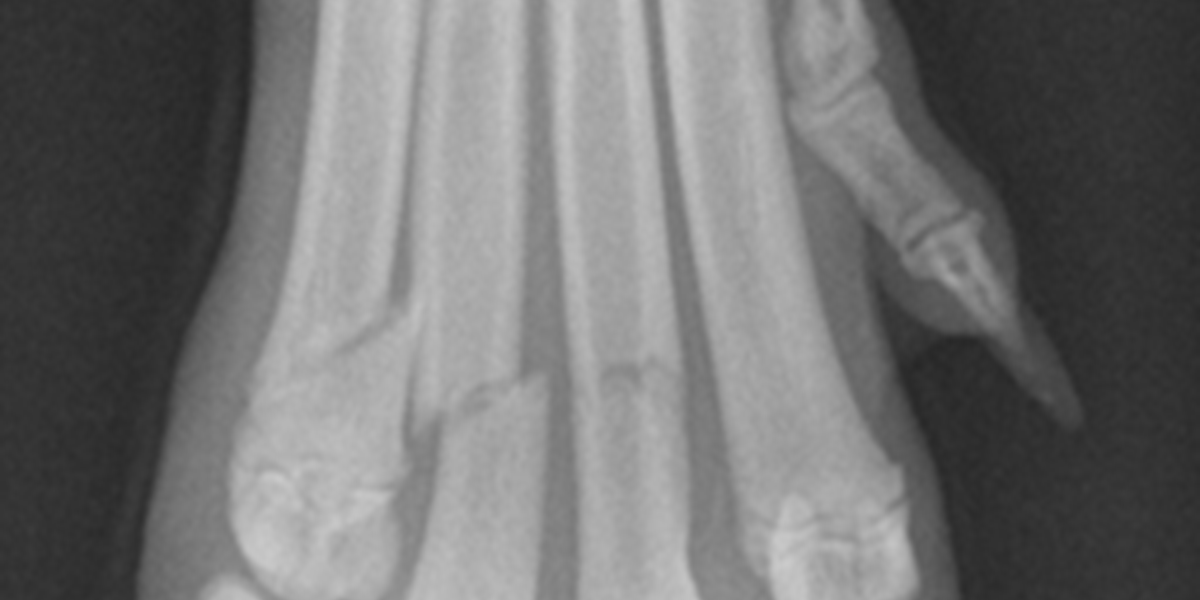

Therapeutic Laser Top Tip I Fractures

Photobiomodulation plays are role in activating osteogenic factors, stimulating osteoblastic cells and accelerating bone healing. MLS® Laser Therapy can be included in the treatment of surgically fixated fractures or delayed/non-union.